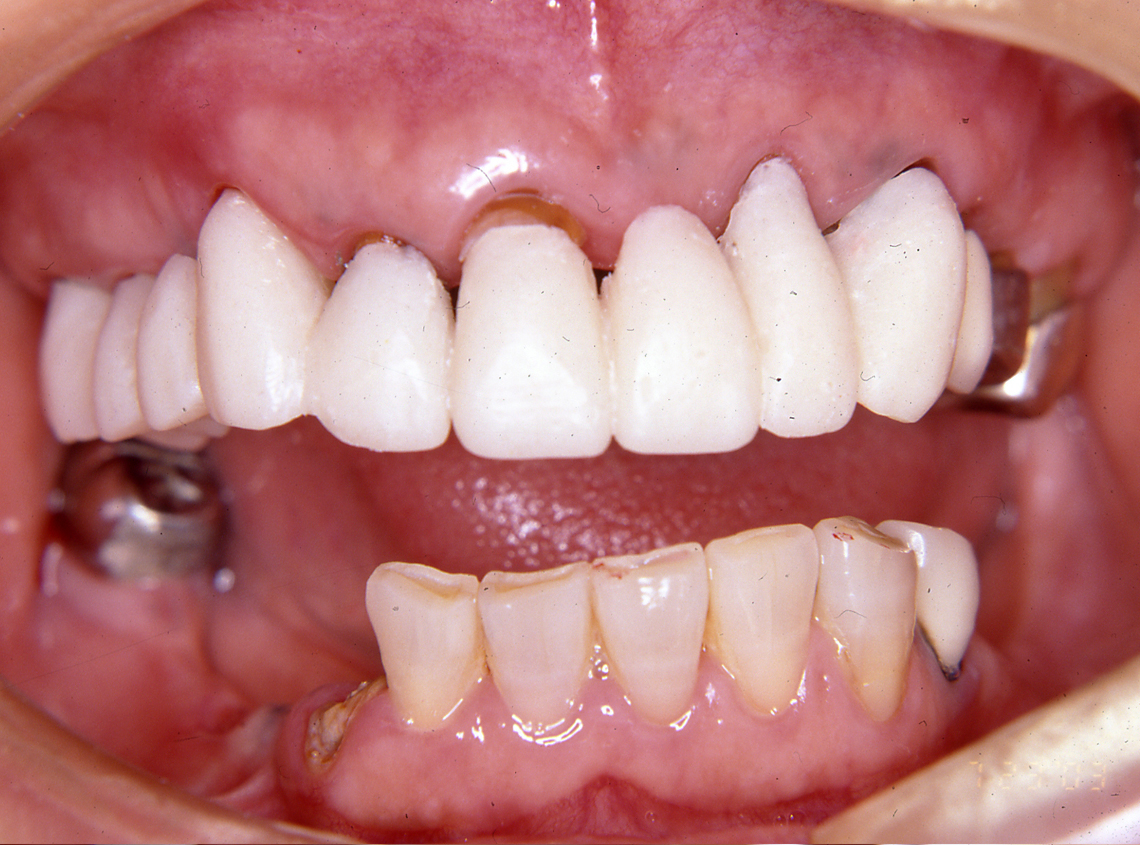

患 者 : S.K様 女性

主 訴 : 補綴物破損、義歯不適による咀嚼障害のためインプラント治療希望

初診日 : 2003年07月11日

1.初診時(2003年)

2.ブリッジ除去後治療用仮歯のブリッジ装着